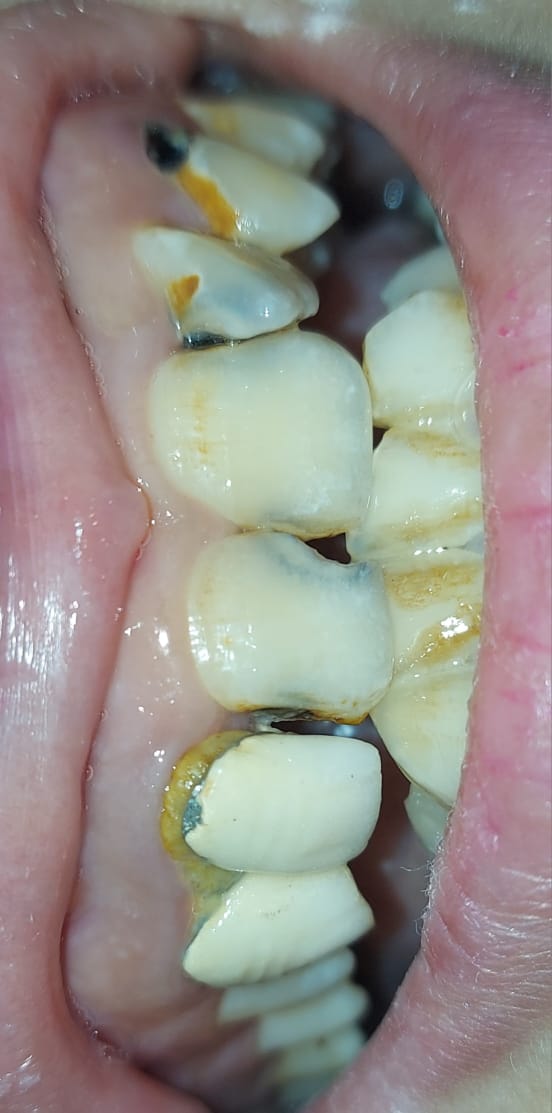

Published September 22, 2023 at 552 × 1113 in Cervical Caries: Causes, Symptoms, Prevention, and Treatment.

18 year old female presented with chief complaint of caries involving multiple teeths